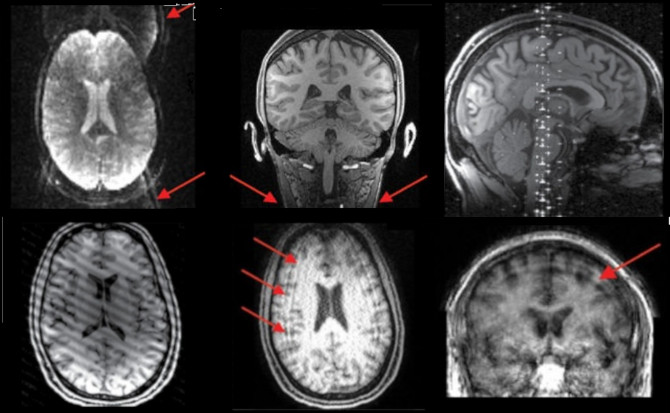

Korekcija pokreta. Prvi korak koji je od suštinskog značaja za sve rsfMRI podatke je korekcija pokreta, čiji je cilj ispravljanje efekta kretanja glave subjekta u skeneru. Niko ne može mirno ležati u skeneru i uvek postoje barem male količine pokreta glave.

Korekcija pokreta funkcioniše tako što prostorno registruje svaku zapreminu zasebno na odabranu referentnu zapreminu. Referentni volumen je obično jedan od dobijenih volumena (bilo prvi ili srednji volumen). Međutim, ponekad je bolje koristiti alternativnu sliku kao referencu; kao u višepojasnoj sekvenci treba koristiti nesaturisanu sliku, jer pruža bolji kontrast tkiva od drugih volumena (SBref). Korekcija pokreta primenjuje transformacije na svaki volumen tako da se svi rezultujući volumeni prostorno uparuju.